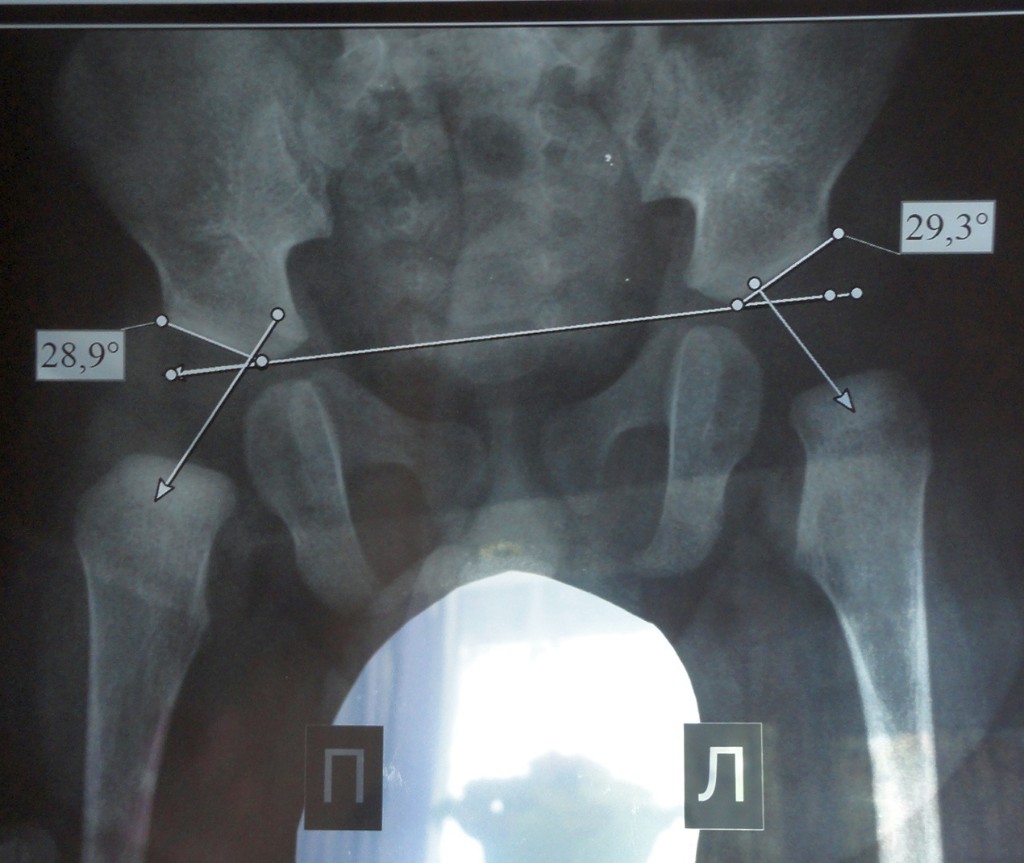

Оссификация тазобедренных суставов: что это и как проявляется?